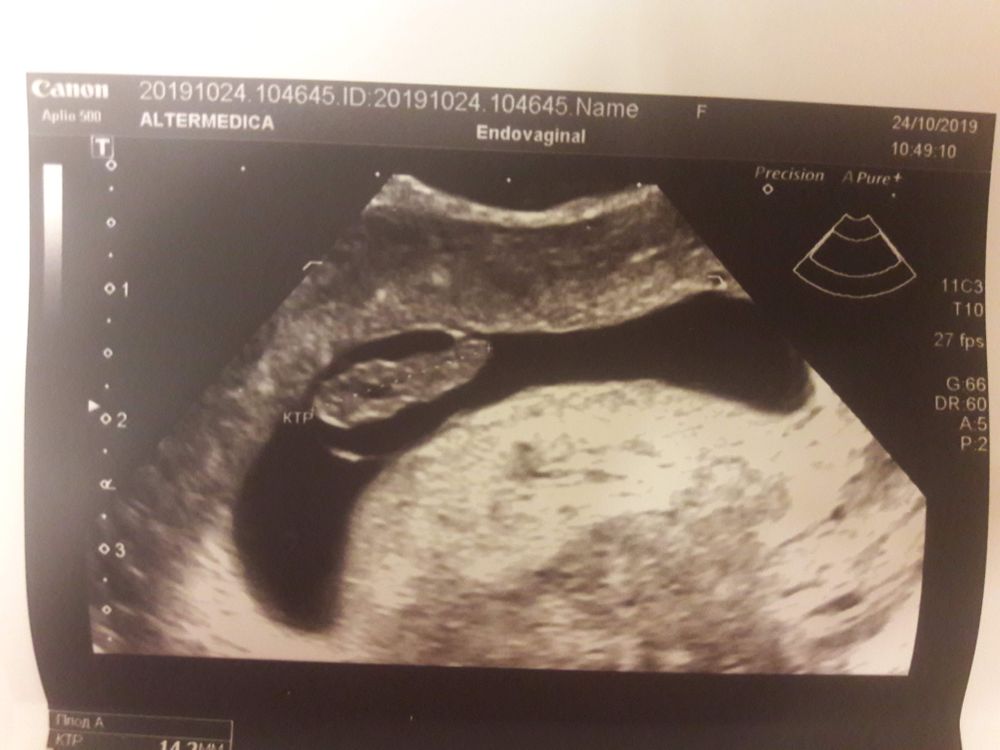

У меня с первой беременностью был гипертонус по задней стенке и помню полело именно в области копчика. Всю беременность от тонуса мучилась и постоянно принимала ношпу и магне B6. Вот такое к меня было УЗИ.